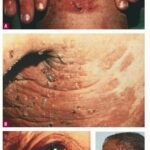

The classic presentation is of a noninflammatory bullous disease with an acral distribution that heals with scarring and milia formation. This presentation is reminiscent of porphyria cutanea tarda when it is mild and of the hereditary form of recessive dystrophic EB when it is severe . The classic form of EBA is thus a mechanobullous disease marked by skin fragility. These patients have erosions, tense blisters within noninflamed skin, and scars over trauma-prone surfaces such as the backs of the hands, knuckles, elbows, knees, sacral area, and toes . Some blisters may be hemorrhagic or develop scales, crusts, or erosions. The lesions heal with scarring and frequently with the formation of pearl-like milia cysts within the scarred areas . Although this presentation may be reminiscent of PCT, these patients do not have other hallmarks of PCT, such as hirsutism, a photodistribution of the eruption, or scleroderma-like changes, and their urinary porphyrins are within normal limits. A scarring alopecia and some degree of nail dystrophy may be seen.

Bullous Pemphigoid-Like Presentation A second clinical presentation of EBA is of a widespread, inflammatory vesiculobullous eruption involving the trunk, central body, and skin folds in addition to the extremities.15 The bullous lesions are tense and surrounded by inflamed or even urticarial skin. Large areas of inflamed skin may be seen without any blisters and only erythema or urticarial plaques. These patients often complain of pruritus and do not demonstrate prominent skin fragility, scarring, or milia formation. This clinical constellation is more reminiscent of BP than a mechanobullous disorder. Similar to BP, the distribution of the lesions may show an accentuation within flexural areas and skin folds.

Brunsting-Perry cicatricial BP is a chronic, recurrent vesiculobullous eruption localized to the head and neck and characterized by residual scars, sub-epidermal bullae, IgG deposits at the DEJ, and minimal or no mucosal involvement. The antigenic target for the IgG autoantibodies, however, has not been defined. Nevertheless, a patient reported with this constellation of findings had IgG autoantibodies directed to anchoring fibrils below the lamina densa.We have seen three additional patients with the features of Brunsting-Perry pemphigoid and autoantibodies directed to type VII collagen (unpublished observations). Therefore, it appears that EBA patients may present with a clinical phenotype of Brunsting-Perry pemphigoid .

According to the authors’ experience, approximately 25 percent of patients with EBA may present with a BP-like clinical appearance. The disease of some of these patients eventually smolders into a more noninflammatory mechanobullous form. However, both the classic and BP-like forms of the disease may co-exist in the same patient . The clinical phenotype of EBA that is reminiscent of pure CP occurs in fewer than 10 percent of all EBA cases.

EBA patients may have many physical findings similar to patients with hereditary dystrophic EB due to gene defects in the type VII collagen gene. These include oral erosions, esophageal strictures, hypo- and hyperpigmentation skin mottling, nail loss, milia formation, scarring, and a degree of fibrosis of the hands.